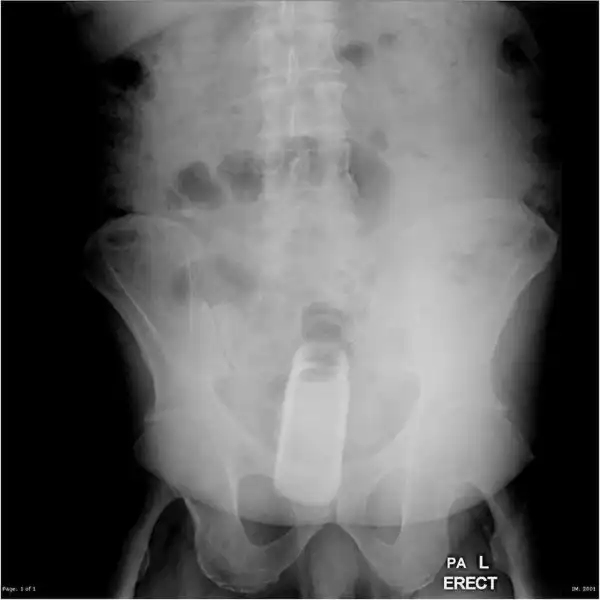

Врачебные находки в интимных местах

Или как впихнуть невпихуемое :lol: